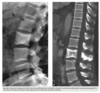

An anteroposterior view of the pelvis

(Fig. 2.24.1) in an elderly man shows extensive thick-

ening of the right iliopectineal line (arrows) with

coarsening of the trabecular pattern and increased

sclerosis throughout the entire right hemipelvis.

Paget disease (i.e., osteitis deformans)

disordered bone

remodeling affecting osteoblastic and osteoclastic

activity. Osseous involvement may be monostotic

or polyostotic, and 80% of the patients are asymp-

tomatic at the time of the discovery of the disease,

usually as an incidental finding on radiography or

because of elevated serum alkaline phosphatase and

elevated serum and urinary hydroxyproline.

stage I (acute phase), active and unbalanced osteo-

clastic bone resorption usually causes areas of lytic

bone destruction. In stage II (intermediate phase),

increased osteoblastic activity results in thickening of the cortex, coarsening of the trabecular pattern,

generalized bone overgrowth, and loss of corticome-

dullary differentiation. In stage III (late or inactive

phase), there is a diffuse increase in the density of

involved bone. Stage IV is the superimposed malig-

nant degeneration of Paget disease into a osteosarcoma.

radiographic findings in the acute phase are

osteoporosis circumscripta, in which an advancing

lytic area is seen in the frontal or occipital regions of

the skull, and subarticular osteolysis in the diaphy-

ses of the tubular bones, especially the tibia, yield-

ing a flame-shaped or “blade-of-grass” appearance

(Fig. 2.24.2). In the intermediate stage, there may

be bowing of the long bones, an “ivory” or “pic-

ture frame” vertebral body (Fig. 2.24.3), and more

extensive calvarial osteosclerosis superimposed on

a background of osteolysis, resulting in the cotton-

wool appearance of the skull.

In the long bones of the lower extremity, corti-

cal thickening, increased trabecular coarseness, and

bowing can be seen (Fig. 2.24.5), and CT can confirm

these findings (Fig. 2.24.6).